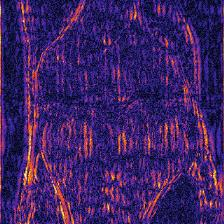

Recently, deep neural networks have greatly advanced undersampled Magnetic Resonance Image (MRI) reconstruction, wherein most studies follow the one-anatomy-one-network fashion, i.e., each expert network is trained and evaluated for a specific anatomy. Apart from inefficiency in training multiple independent models, such convention ignores the shared de-aliasing knowledge across various anatomies which can benefit each other. To explore the shared knowledge, one naive way is to combine all the data from various anatomies to train an all-round network. Unfortunately, despite the existence of the shared de-aliasing knowledge, we reveal that the exclusive knowledge across different anatomies can deteriorate specific reconstruction targets, yielding overall performance degradation. Observing this, in this study, we present a novel deep MRI reconstruction framework with both anatomy-shared and anatomy-specific parameterized learners, aiming to "seek common ground while reserving differences" across different anatomies.Particularly, the primary anatomy-shared learners are exposed to different anatomies to model flourishing shared knowledge, while the efficient anatomy-specific learners are trained with their target anatomy for exclusive knowledge. Four different implementations of anatomy-specific learners are presented and explored on the top of our framework in two MRI reconstruction networks. Comprehensive experiments on brain, knee and cardiac MRI datasets demonstrate that three of these learners are able to enhance reconstruction performance via multiple anatomy collaborative learning.

翻译:最近,深心神经网络大大推进了未经充分取样的磁共振成像(MRI)重建,其中大多数研究都遵循单一解剖一个网络的方式,即每个专家网络都经过特定解剖学的培训和评价。除了在培训多种独立模型方面效率低下之外,这种公约忽视了不同解剖学中共享的、可相互受益的解析知识。为了探索共享知识,一种天真的方法是将各解剖学家的所有数据结合起来,以训练一个全方位网络。不幸的是,尽管存在共享的解析知识,但我们发现,不同解剖学的独家知识可以恶化具体的重建目标,导致总体性能退化。在这项研究中,我们提出了一个新型的深度解剖重建框架,既有解剖学共享知识,又具有具体的解剖学参数,目的是“寻找共同的土壤,同时保留不同解剖学家之间的差异。此外,主要的解剖学学习者将接触不同的解剖学数据,通过多种解剖学重建的模型,并用不同的解剖学研究者将数据展示出一个全方位基础。